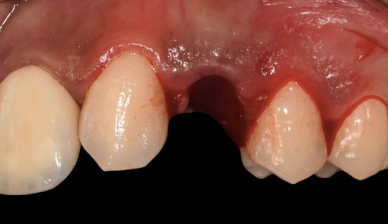

The patient presented with agenesis (congenital absence) of the upper left first premolar and the upper right lateral incisor. Previous orthodontic treatment had addressed the spacing, and the lateral incisor site had been left unrestored. Over time, the upper left canine (UL3) had drifted significantly into the wrong position.

The decision was made to extract the displaced UL3 and place an implant at the same site — an immediate placement following extraction. This type of case demands precision: the implant position has to be driven by the final prosthetic outcome, not just the available bone. Get the angle or position wrong by a couple of millimetres and the restoration either looks wrong, functions poorly, or both.

Initial clinical situation showing displaced upper left canine Initial occlusal view of the displaced canine site

Initial situation The upper left canine has drifted into the premolar space following orthodontic treatment. The decision was made to extract and place an implant, driven by the final prosthetic position.